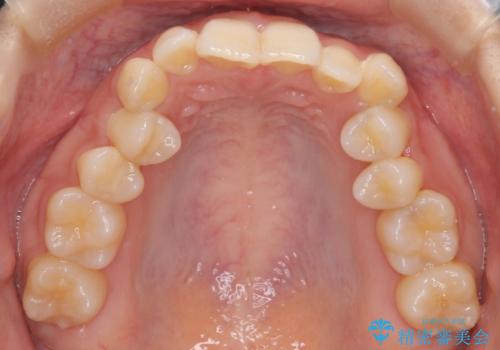

ディープバイト改善のためのインビザライン治療

- 患者様は、全体的な歯列のガタガタとディープバイト(深い噛み合わせ)を主訴として来院されました。診断の結果、ディープバイトを改善するためには、歯列全体の拡大が必要であると判断しました。治療には、透明なマウスピース型矯正装置「インビザライン」を使用し、歯を適切に拡大しながら歯並びを整える計画を立てました。治療期間はおおよそ2年を見込んで進め、最終的に見た目にも大きく変化をもたらすことを目指しました。

ディープバイトの治療には、奥歯の高さや前歯の位置に対する繊細な調整が必要です。本症例では、インビザラインによる歯列拡大を行うことで、噛み合わせを改善し、歯並び全体を整えました。治療過程では、歯間のスペースを確保するため、IPR(インタープロキシマルリダクション)を適宜行い、無理なく歯列の調整を行いました。治療後は、歯並びが大きく改善され、患者様の見た目にも大きな変化が現れました。インビザラインは透明で目立たず、治療中の見た目を気にされる患者様にも配慮した治療法です。